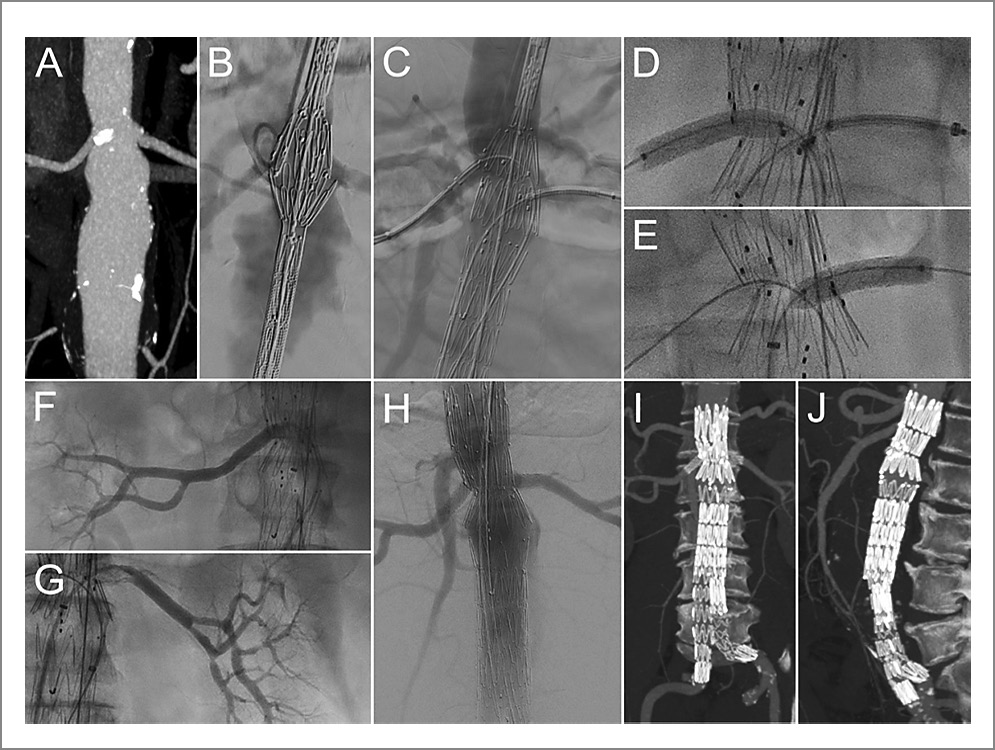

Для точности позиционирования применялось программное обеспечение 3D Fusion. Так, I этапом по сверхжесткому проводнику Lunderquist® (Сook Medical, США) в брюшной отдел аорты заведен фенестрированный компонент. Далее выполнено его частичное раскрытие. После через интродьюсеры 7 Fr катетеризированы правая и левая ПА c последовательной имплантацией в них стент-графтов Bentley (InnoMed GmbH, Германия) 6,0×58 и 6,0×28 мм соответственно. Следующим шагом выполнено полное раскрытие фенестрированного компонента с подтвержденной проходимостью обеих ПА и брыжеечной артерии по данным аортографии. Следующий, II этап включал позиционирование и имплантацию бифуркационного компонента с перекрытием раннее установленного ФЭГ по дистальному краю, имплантацию контралатеральной бранши и постдилатацию компонентов и зон перекрытия баллонным катетером Reliant. При контрольной интраоперационной аортографии выявлено полное выключение АБА из магистрального кровотока с сохранением кровотока по всем висцеральным артериям. Ход оперативного вмешательства представлен на рис. 2.

Рис. 2. Клинический пример 2. ЭВП заранее подготовленным ФЭГ: А – МСКТ-АГ брюшной аорты, прямая проекция; В – начальный этап имплантации: открыто 1-е звено и частично раскрыто 2-е, совмещены метки ЭВПр с устьями артерий; С – имплантация ЭГ без раскрытия проксимальной короны, катетеризированы устья ПА, заведены интродьюсеры 7 Fr; D, E – последовательная имплантация стент-графтов в ПА; F – баллонная дилатация ЭВПр; G – контрольная аортография: позиция ЭГ удовлетворительная, аневризма выключена из кровотока; H, I – контрольная МСКТ-АГ в госпитальный период: отмечается полное выключение аневризмы из кровотока

Гемостаз мест доступов выполнен с помощью систем для ушивания ProGlide. Время рентгеноскопии составило 102 мин, объем контрастного вещества – 280 мл. По данным контрольной госпитальной МСКТ-АГ аневризма выключена из кровотока, подтеканий не отмечалось. На 4-е сутки после хирургического вмешательства пациент в удовлетворительном состоянии выписан под наблюдение по месту жительства.